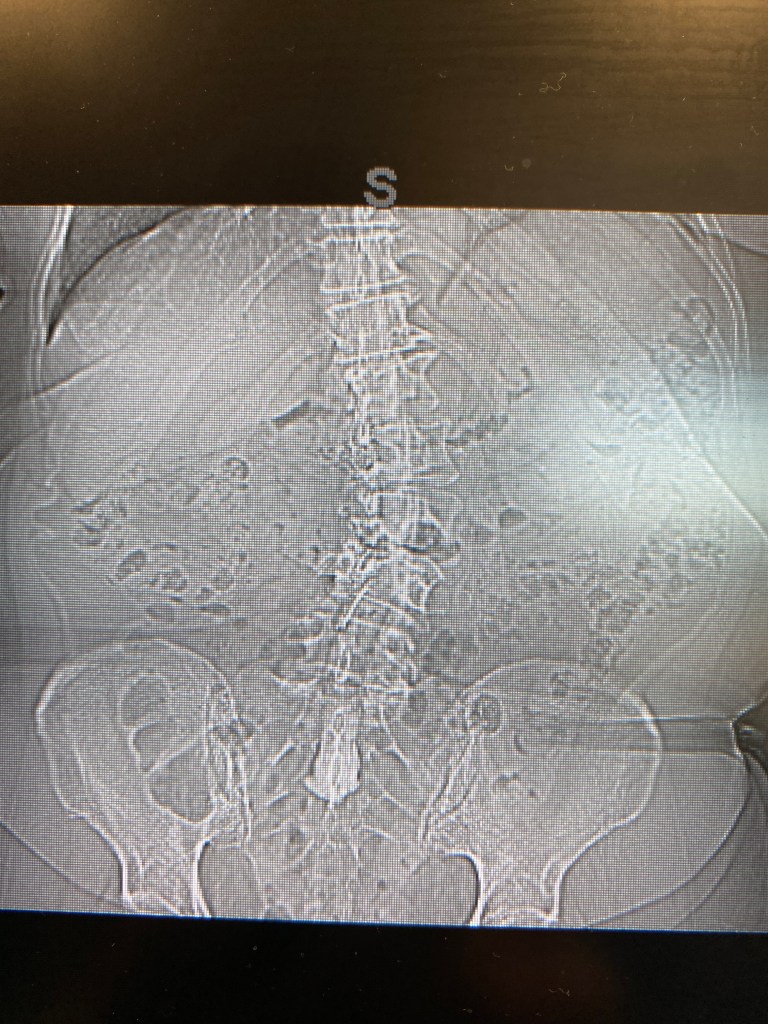

Not this part…

not even the trainwreck in the middle, just one key spot.

The x-rays are this side of obscene, but the amazing fact is that I stand straight… I just can’t keep moving for more than a few minutes.